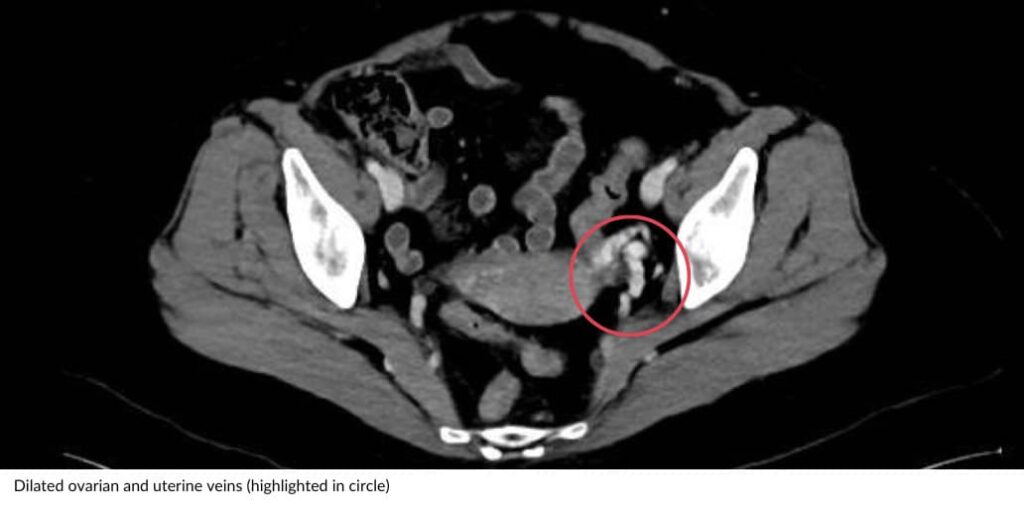

Sometimes ultrasound alone may not provide all the necessary information and your doctor may want additional imaging such as a CT scan or MRI. Both CT and MRI are used to visualise the abnormal veins within the pelvis, their size, location and severity. Also can be used to look for other abnormalities that may be causing the pain and evaluate the surrounding structures in the pelvis.

Dilated ovarian veins